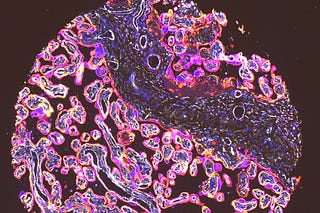

How do you use a virtual cell to do something actually useful? (3/3)

Virtual perturbations that shift T cell effector state in humans

How do you use a virtual cell to do something actually useful? (2/3)

Refining clinical trial eligibility to the right subgroups

How do you use a virtual cell to do something actually useful? (1/3)

Identifying anti-PD1 responders